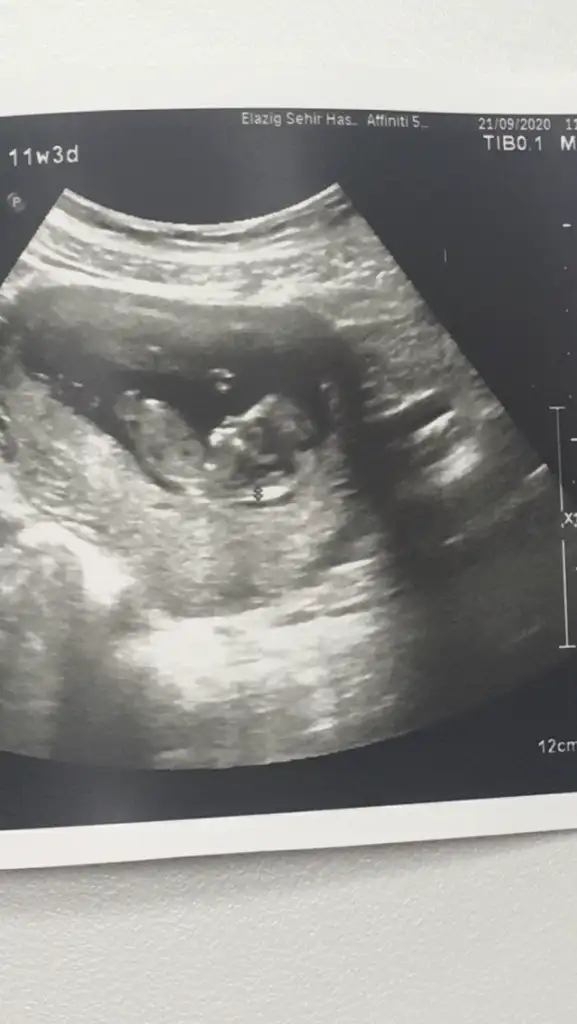

Erkek mi dediBana da yorum yaparmısınız lütfen. Bugün geldim doktordan. Cinsiyeti söyledi ama kesin olarak bi ay sonra dedi

Çünkü kordonu pipi sanma ihtimalleri varKız dedi ama kesin sonucu bir sonraki randevuda söylicem dedi. Ama emindir bence.14+3 sonuçta. Daha nezaman kesinleşir ki. Değişme ihtimali varmıdır ?

Haa kizmi dedi artık kesin bence bu haftalarda kızda yanılma olmuyorKız dedi ama kesin sonucu bir sonraki randevuda söylicem dedi. Ama emindir bence.14+3 sonuçta. Daha nezaman kesinleşir ki. Değişme ihtimali varmıdır ?

12 haftalığa göre çok net göstermiş masallahUSG 12.3 şimdi 17 haftalik